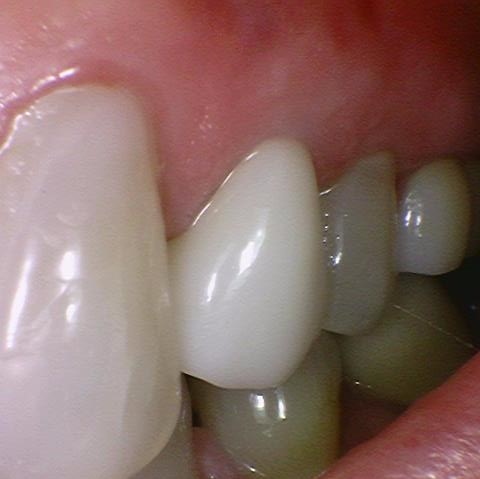

많이 썩은 치아 신경치료 후 지르코니아 크라운 [시청역 연세예감치과]

많이 썩은 치아 신경치료 후 지르코니아크라운[시청역 연세예감치과]